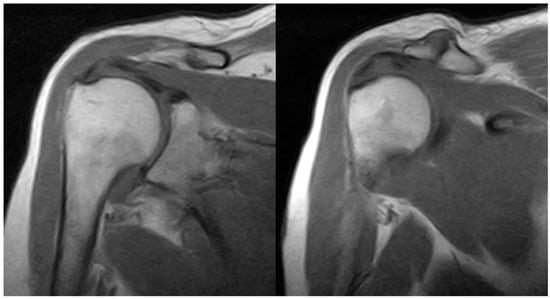

2. Detailed Case Description